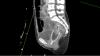

À 15 jours de son admission, la patiente présente un état de choc d’allure septique sans point d’appel clinique évident. Les hémocultures et les prélèvements respiratoires prélevés à cette occasion sont stériles. La patiente est à ce moment-là encore intubée et ventilée mécaniquement. La sédation n’a pas pu être totalement interrompue.

Un scanner thoraco-abdomino-pelvien est réalisé à la recherche d’un foyer infectieux dont voici une coupe sagittale abdomino-pelvienne.